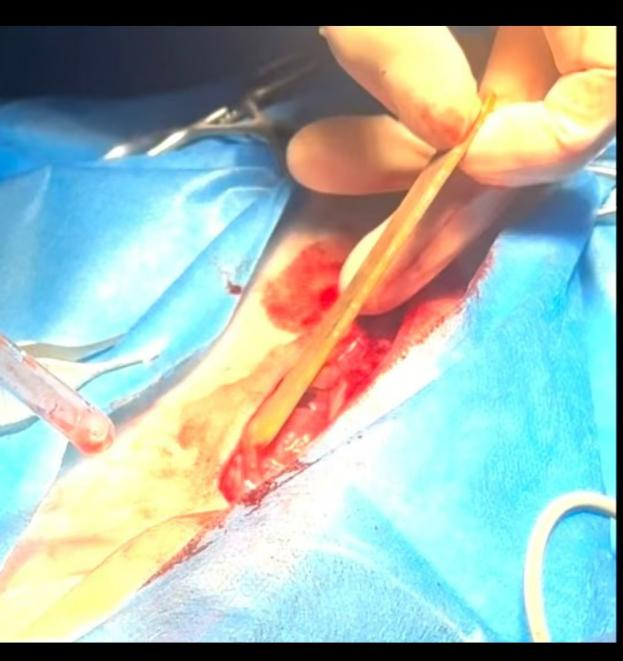

Given the severity of the condition, emergency abdominal surgery was recommended. During surgery, we found that the dog’s abdomen was filled with cloudy fluid, and both the intestines and peritoneum showed signs of significant inflammation. We removed a foreign object—a drinking straw—that had penetrated the intestine and caused a tear, leading to abdominal infection. In addition, the ileocecal junction showed intussusception and necrosis, which required part of the affected intestine to be removed and repaired. The abdomen was thoroughly cleaned to remove contaminants and prevent further infection.